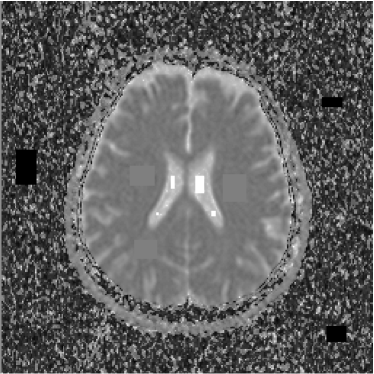

Therefore, the pixels of the ADC map are proportional to the diffusion coefficients in the corresponding voxels. However, as the images are acquired at different moments, there must be considered the occurrence of noise in all the experiments. Furthermore, the presence of noise is amplified by the use of the logarithm. In figures 7 and 8 it is possible to see several artifacts generated by the presence of noise. In regions where signal-to-noise ratio is poor (e.g. s/n1𝑠𝑛1s/n\approx 1), the ADC map produces artifacts as a consequence of the calculation of logarithms (notice equations 4 and 6).

Such factors leave us to the following conclusion: the pixels of the ADC map not necessarily correspond to the diffusion coefficients: several pixels indicate high diffusion rates in voxels where the sample are not present or in very solid areas like bone in the cranial box, as can be seen in figures 7 and 8. This is the reason why such map indicates apparent diffusion coefficients, and not real diffusion coefficients.

Refer to caption

Figure 7: ADC map of 13th slice calculated from the three diffusion images presented in figures 1, 2 and 3